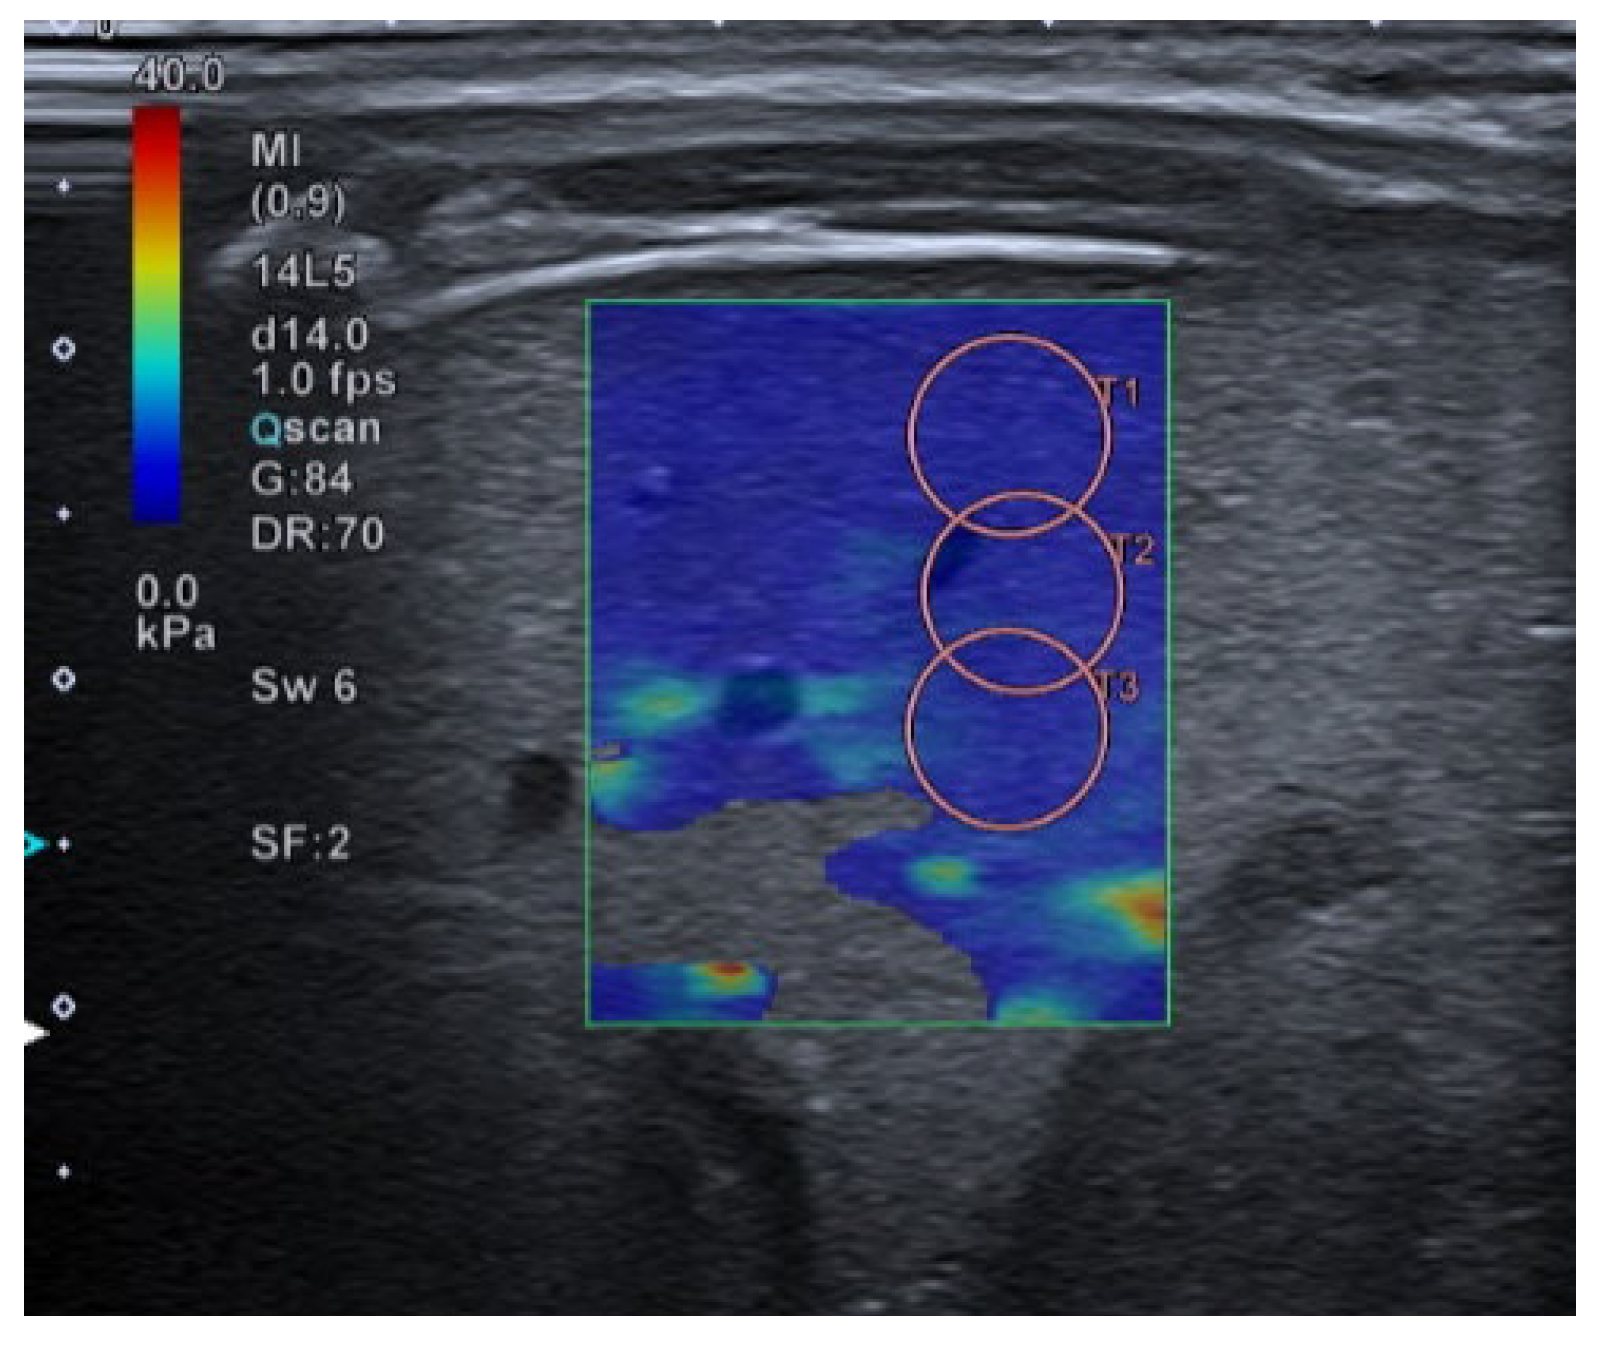

- 2D-Shear Wave Elastography (SWE): This is the latest and newest shear wave imaging technique. Like ARFI or pSWE, it uses acoustic radiation stimulation but, in this case, it rapidly scans multiple focal areas. This creates a virtual cylindrical shear wave cone that allows for the real-time monitoring of shear waves in 2D to measure their velocity, which is displayed on a quantitative colour map superimposed on a B-mode image (Figure 5). SWE has been extensively applied to characterize liver fibrosis [30,31], breast masses [32,33], prostate cancer lesions [34], thyroid nodules [35] and cervical lymph nodes [36]. In these contexts, SWE displayed low variability with respect to SE [37].